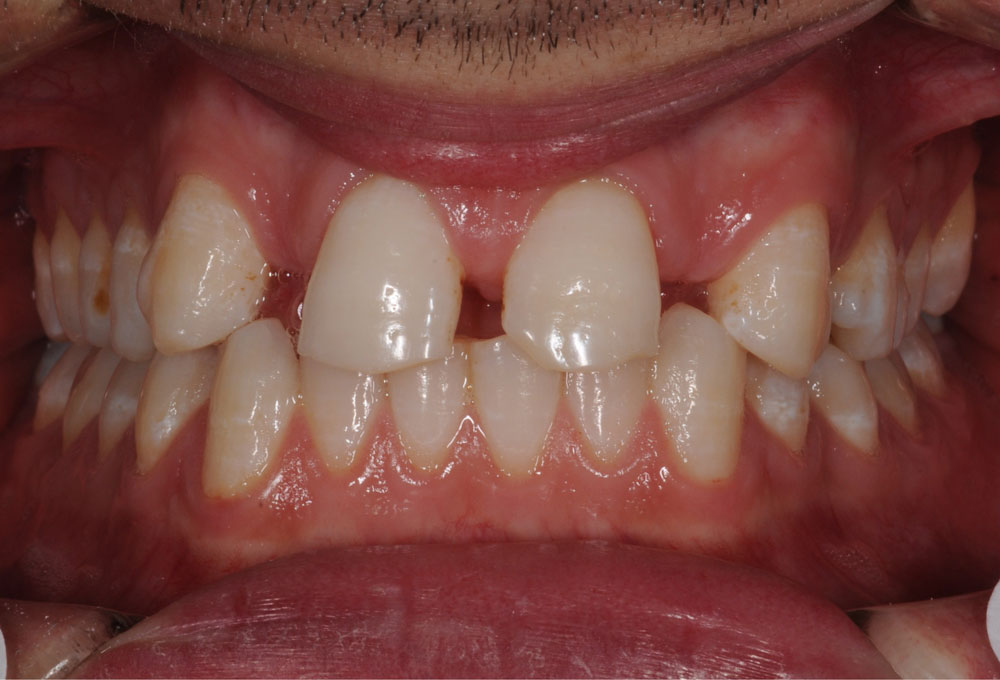

In genere le agenesie dentarie si manifestano con presenza di spazi interdentali.

Le opzioni terapeutiche ortodontiche si possono sintetizzare in:

Il vantaggio principale di questa soluzione è che si può ottenere una buona estetica del sorriso e una corretta funzione masticatoria senza ricorrere a sostituzioni protesiche.

Frequentemente, in questi casi si ricorrere a una finalizzazione estetica con rimodellamento della forma di alcuni elementi dentali (camouflage), per meglio inserirli nel contesto estetico e funzionale orale.